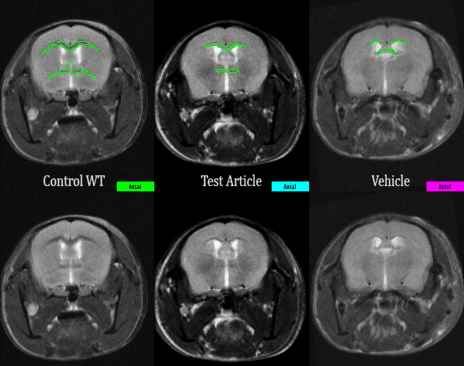

Neurotoxicity

Approximately one quarter of small molecules in drug development intended for CNS indications fail in clinical trials due to neurotoxicity issues, which are often not identified during drug discovery stages.